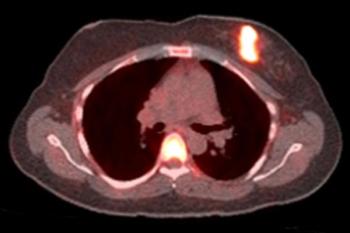

Hormone therapy is only effective in roughly half of estrogen receptor-positive cancers. Being able to identify patients that will not respond could save valuable treatment time.